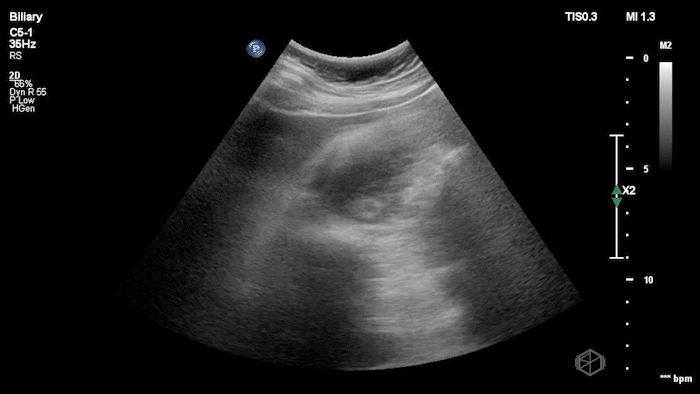

Large mass near the neck of the gallbladder

16A - Same patient, what is the differential diagnosis for this finding?

Questionable stone-in-neck but, does not appear to be internal to the gallbladder; found to be gallbladder carcinoma.